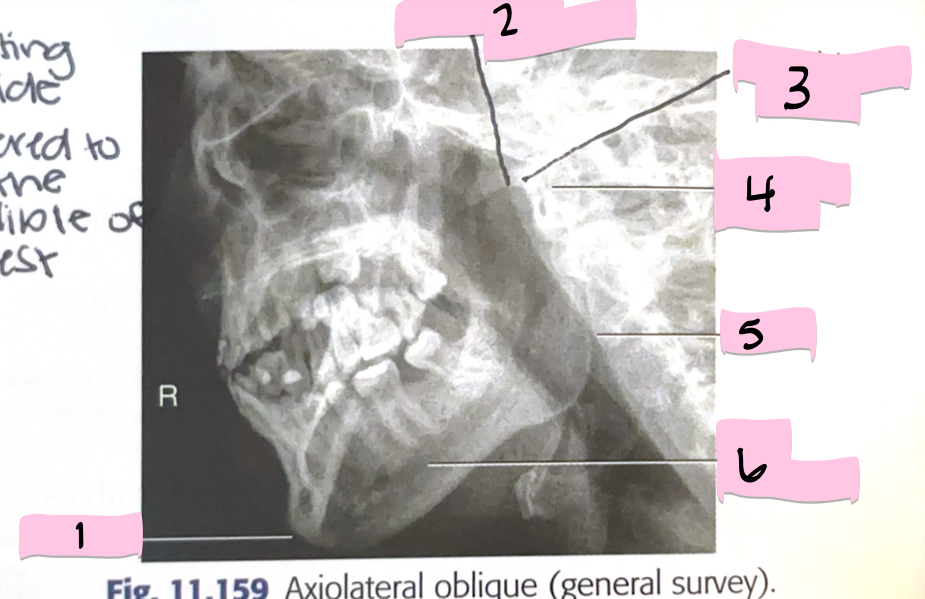

What is 1 pointing to?

Frontal sinus

What is 2 pointing to?

Superior orbital fissure

What is 3 pointing to?

Bony nasal septum

What is 4 pointing to?

Anterior nasal spine

What is 5 pointing to?

Crista galli

What is 6 pointing to?

Petrous ridge

What is 7 pointing to?

Floor of orbit

What is 8 pointing to?

Maxillary sinus